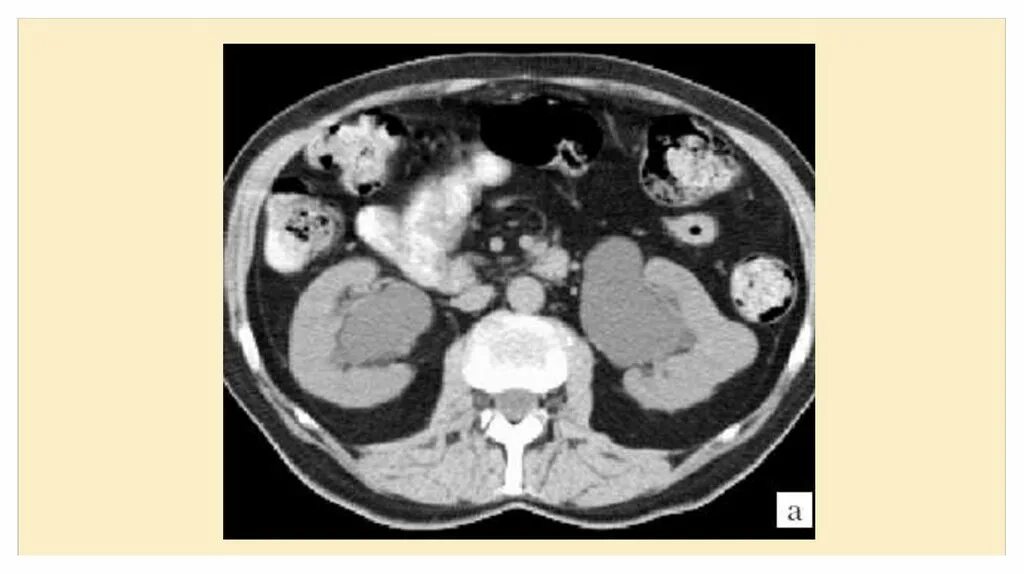

Кортикальная киста почки